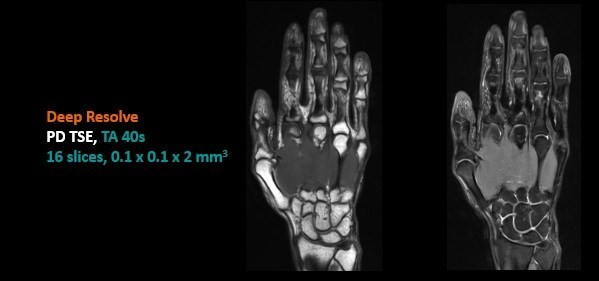

Deep Resolve實(shí)現(xiàn)手部100um超高分辨率成像,將MR影像提高到空前水平